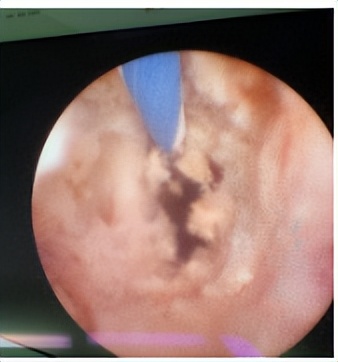

2. 局部损伤:结石会损伤尿路的局部黏膜从而引起血尿,还会刺激黏膜出现炎症、水肿等症状,甚至长出息肉。

(结石造成的输尿管粘膜损伤)